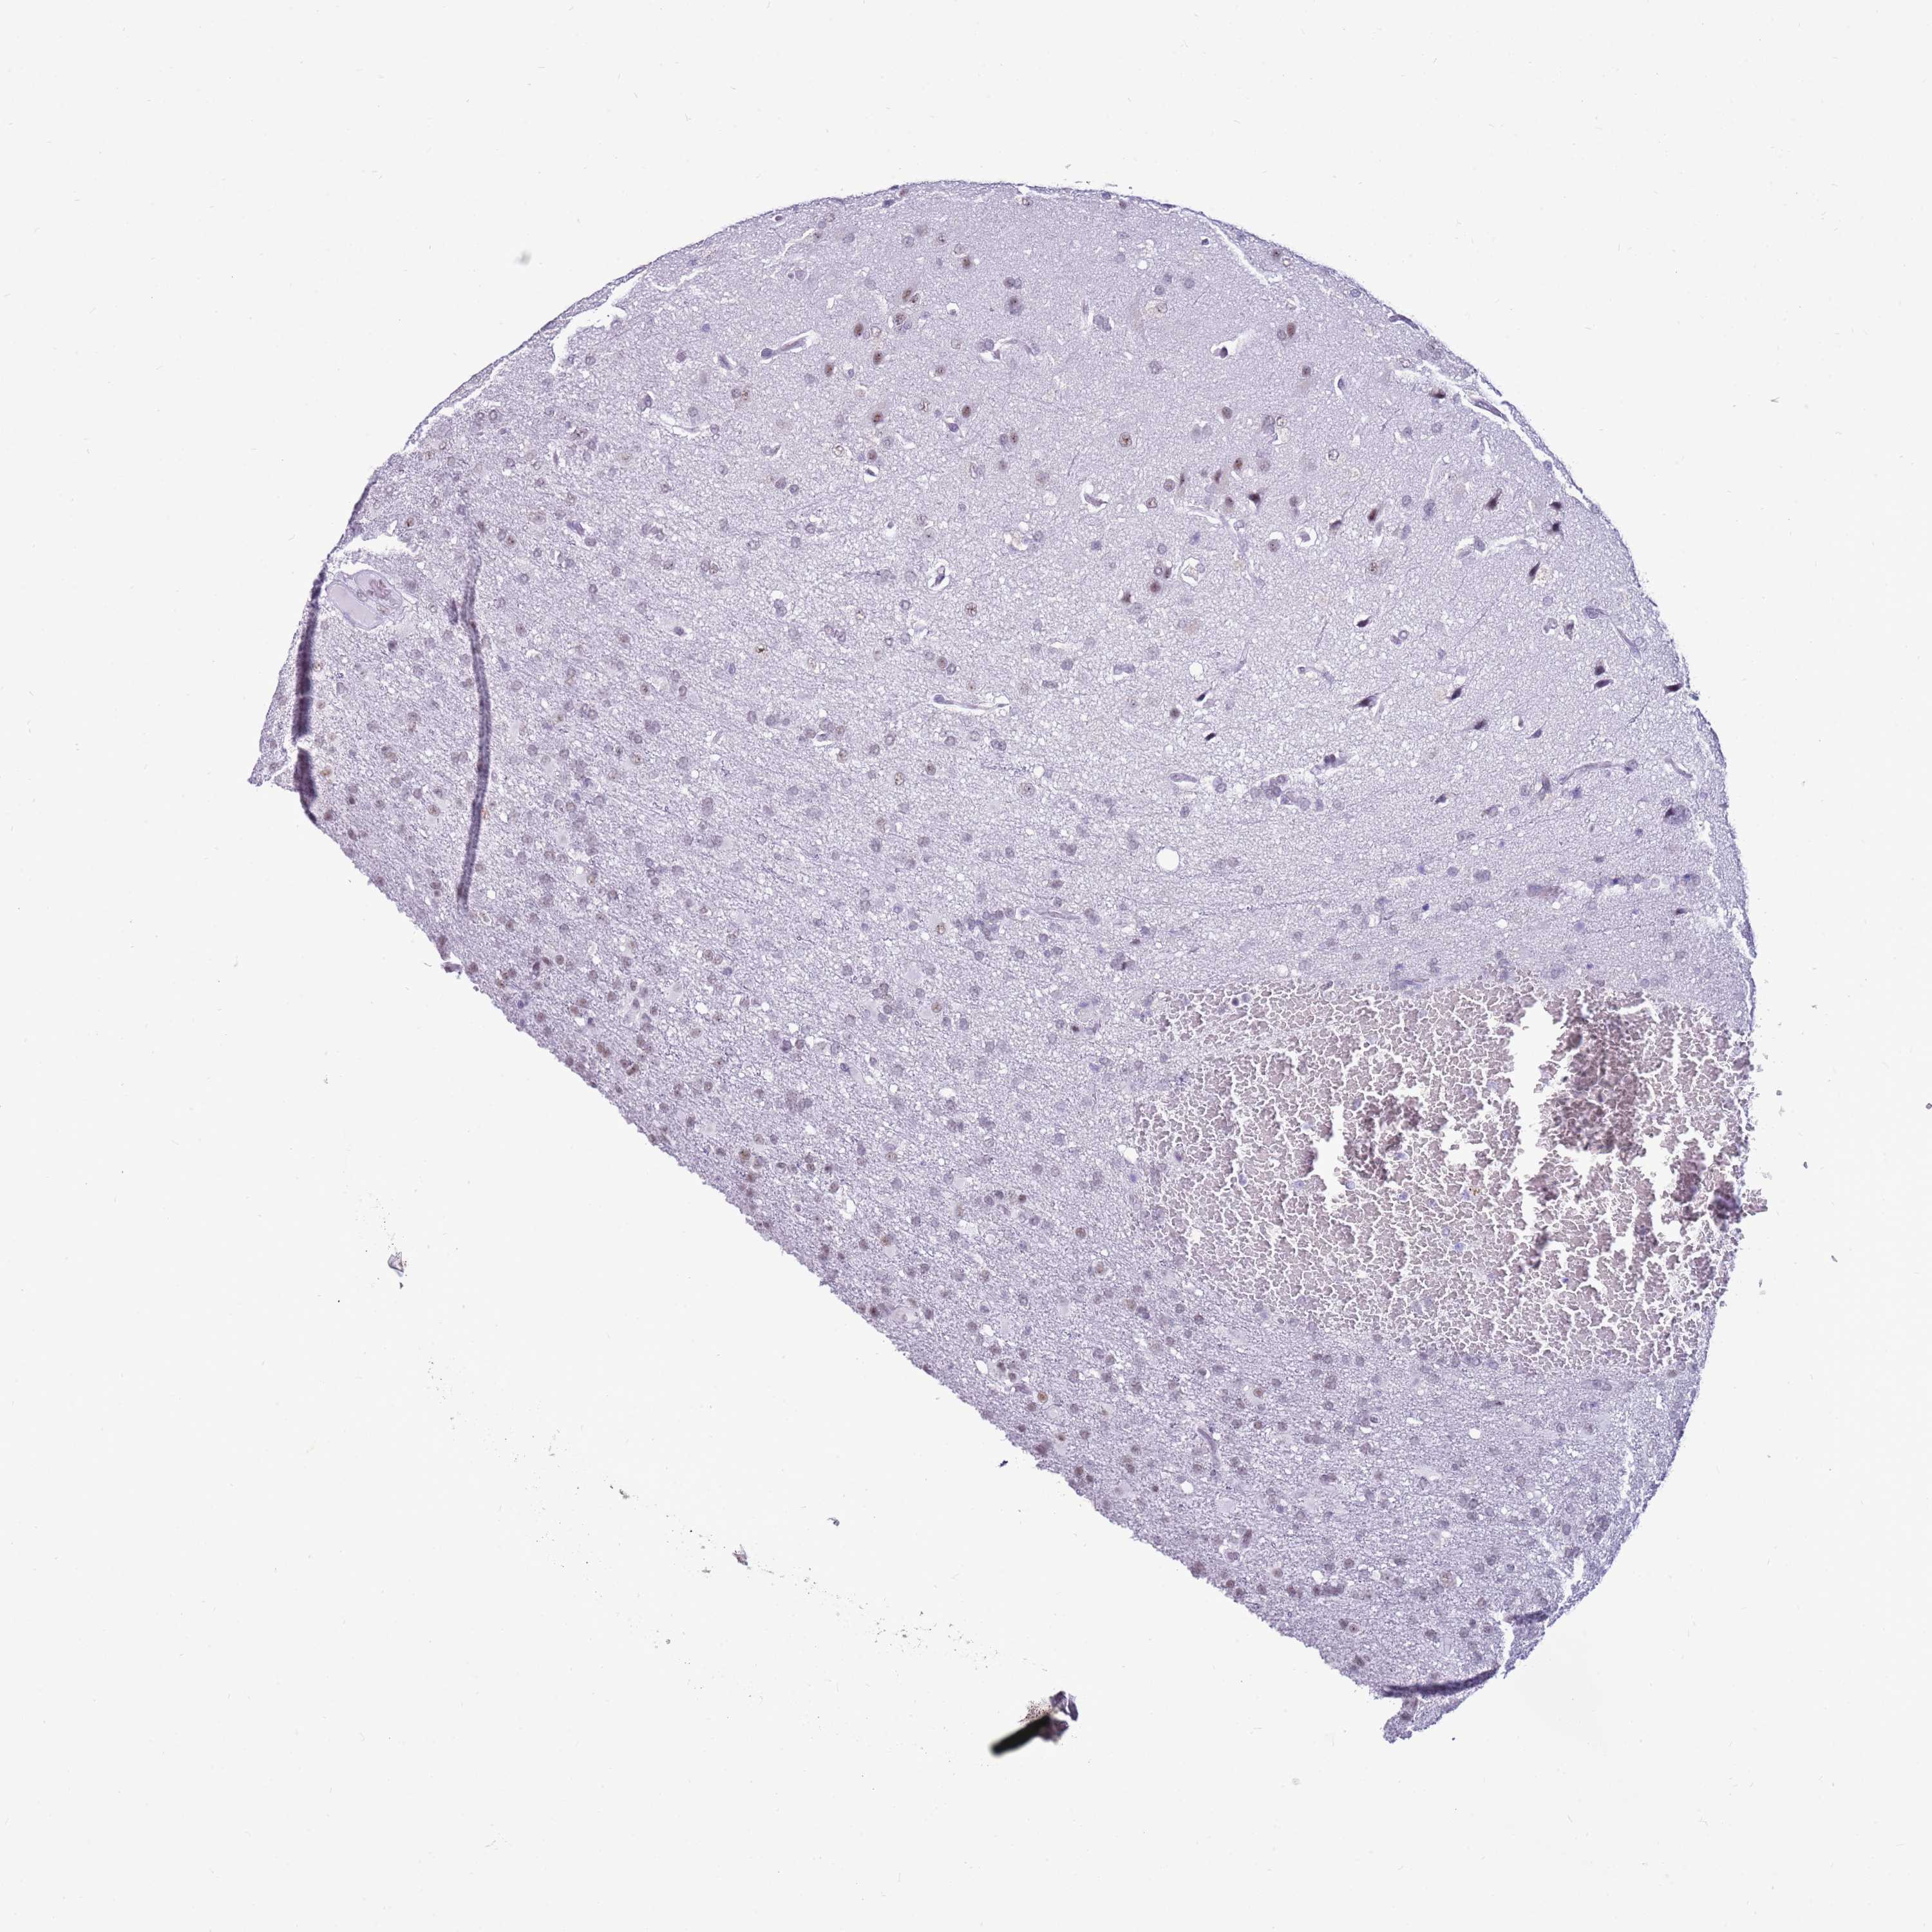

GLIOMA - Protein expressioni

A mouse-over function shows sample information and annotation data. Click on an image to view it in a full screen mode. Samples can be filtered based on level of antibody staining by selecting one or several of the following categories: high, medium, low and not detected. The assay and annotation is described here.

Note that samples used for immunohistochemistry by the Human Protein Atlas do not correspond to samples in the TCGA dataset.

Antibody stainingi

Antibody staining in the annotated cell types in the current human tissue is reported as not detected, low, medium, or high, based on conventional immunohistochemistry profiling in selected tissues. This score is based on the combination of the staining intensity and fraction of stained cells.

Each image is clickable and will lead to virtual microscopy that enables deeper exploration of all samples and also displays staining intensity scores, fraction scores and subcellular localization as well as patient and tissue information for each sample.

Antibody HPA047047

Staining

High

Medium

Low

Not detected

Intensity

Strong

Moderate

Weak

Negative

Quantity

>75%

75%-25%

<25%

None

Location

Nuclear

Cytoplasmic/membranous

Cytoplasmic/membranous,nuclear

Glioma, malignant, High grade

Glioma, malignant, Low grade